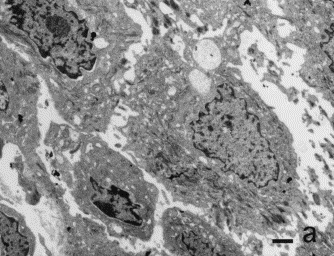

Penfigoide ampolloso. A pequeño aumento (a) y gran aumento (b y c )Se observa la separación dermoepidérmica a nivel de la lámina lúcida (*), Se observa la lámina densa (flechas) que permanece en el suelo de la ampolla. (E:epidermis, D:dermis)